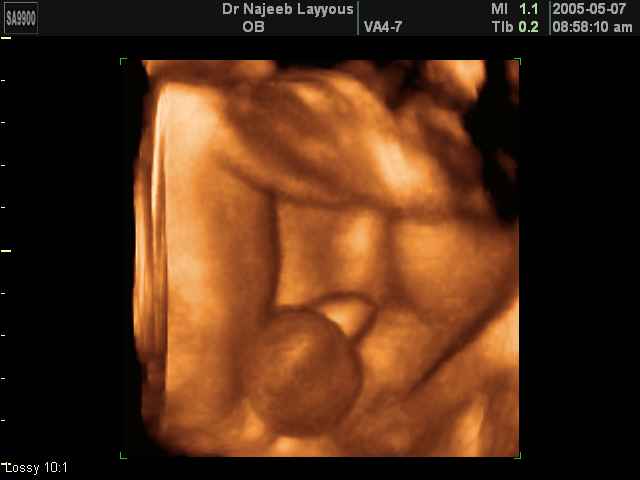

- Fetal Parts Ultrasound Scan Photos